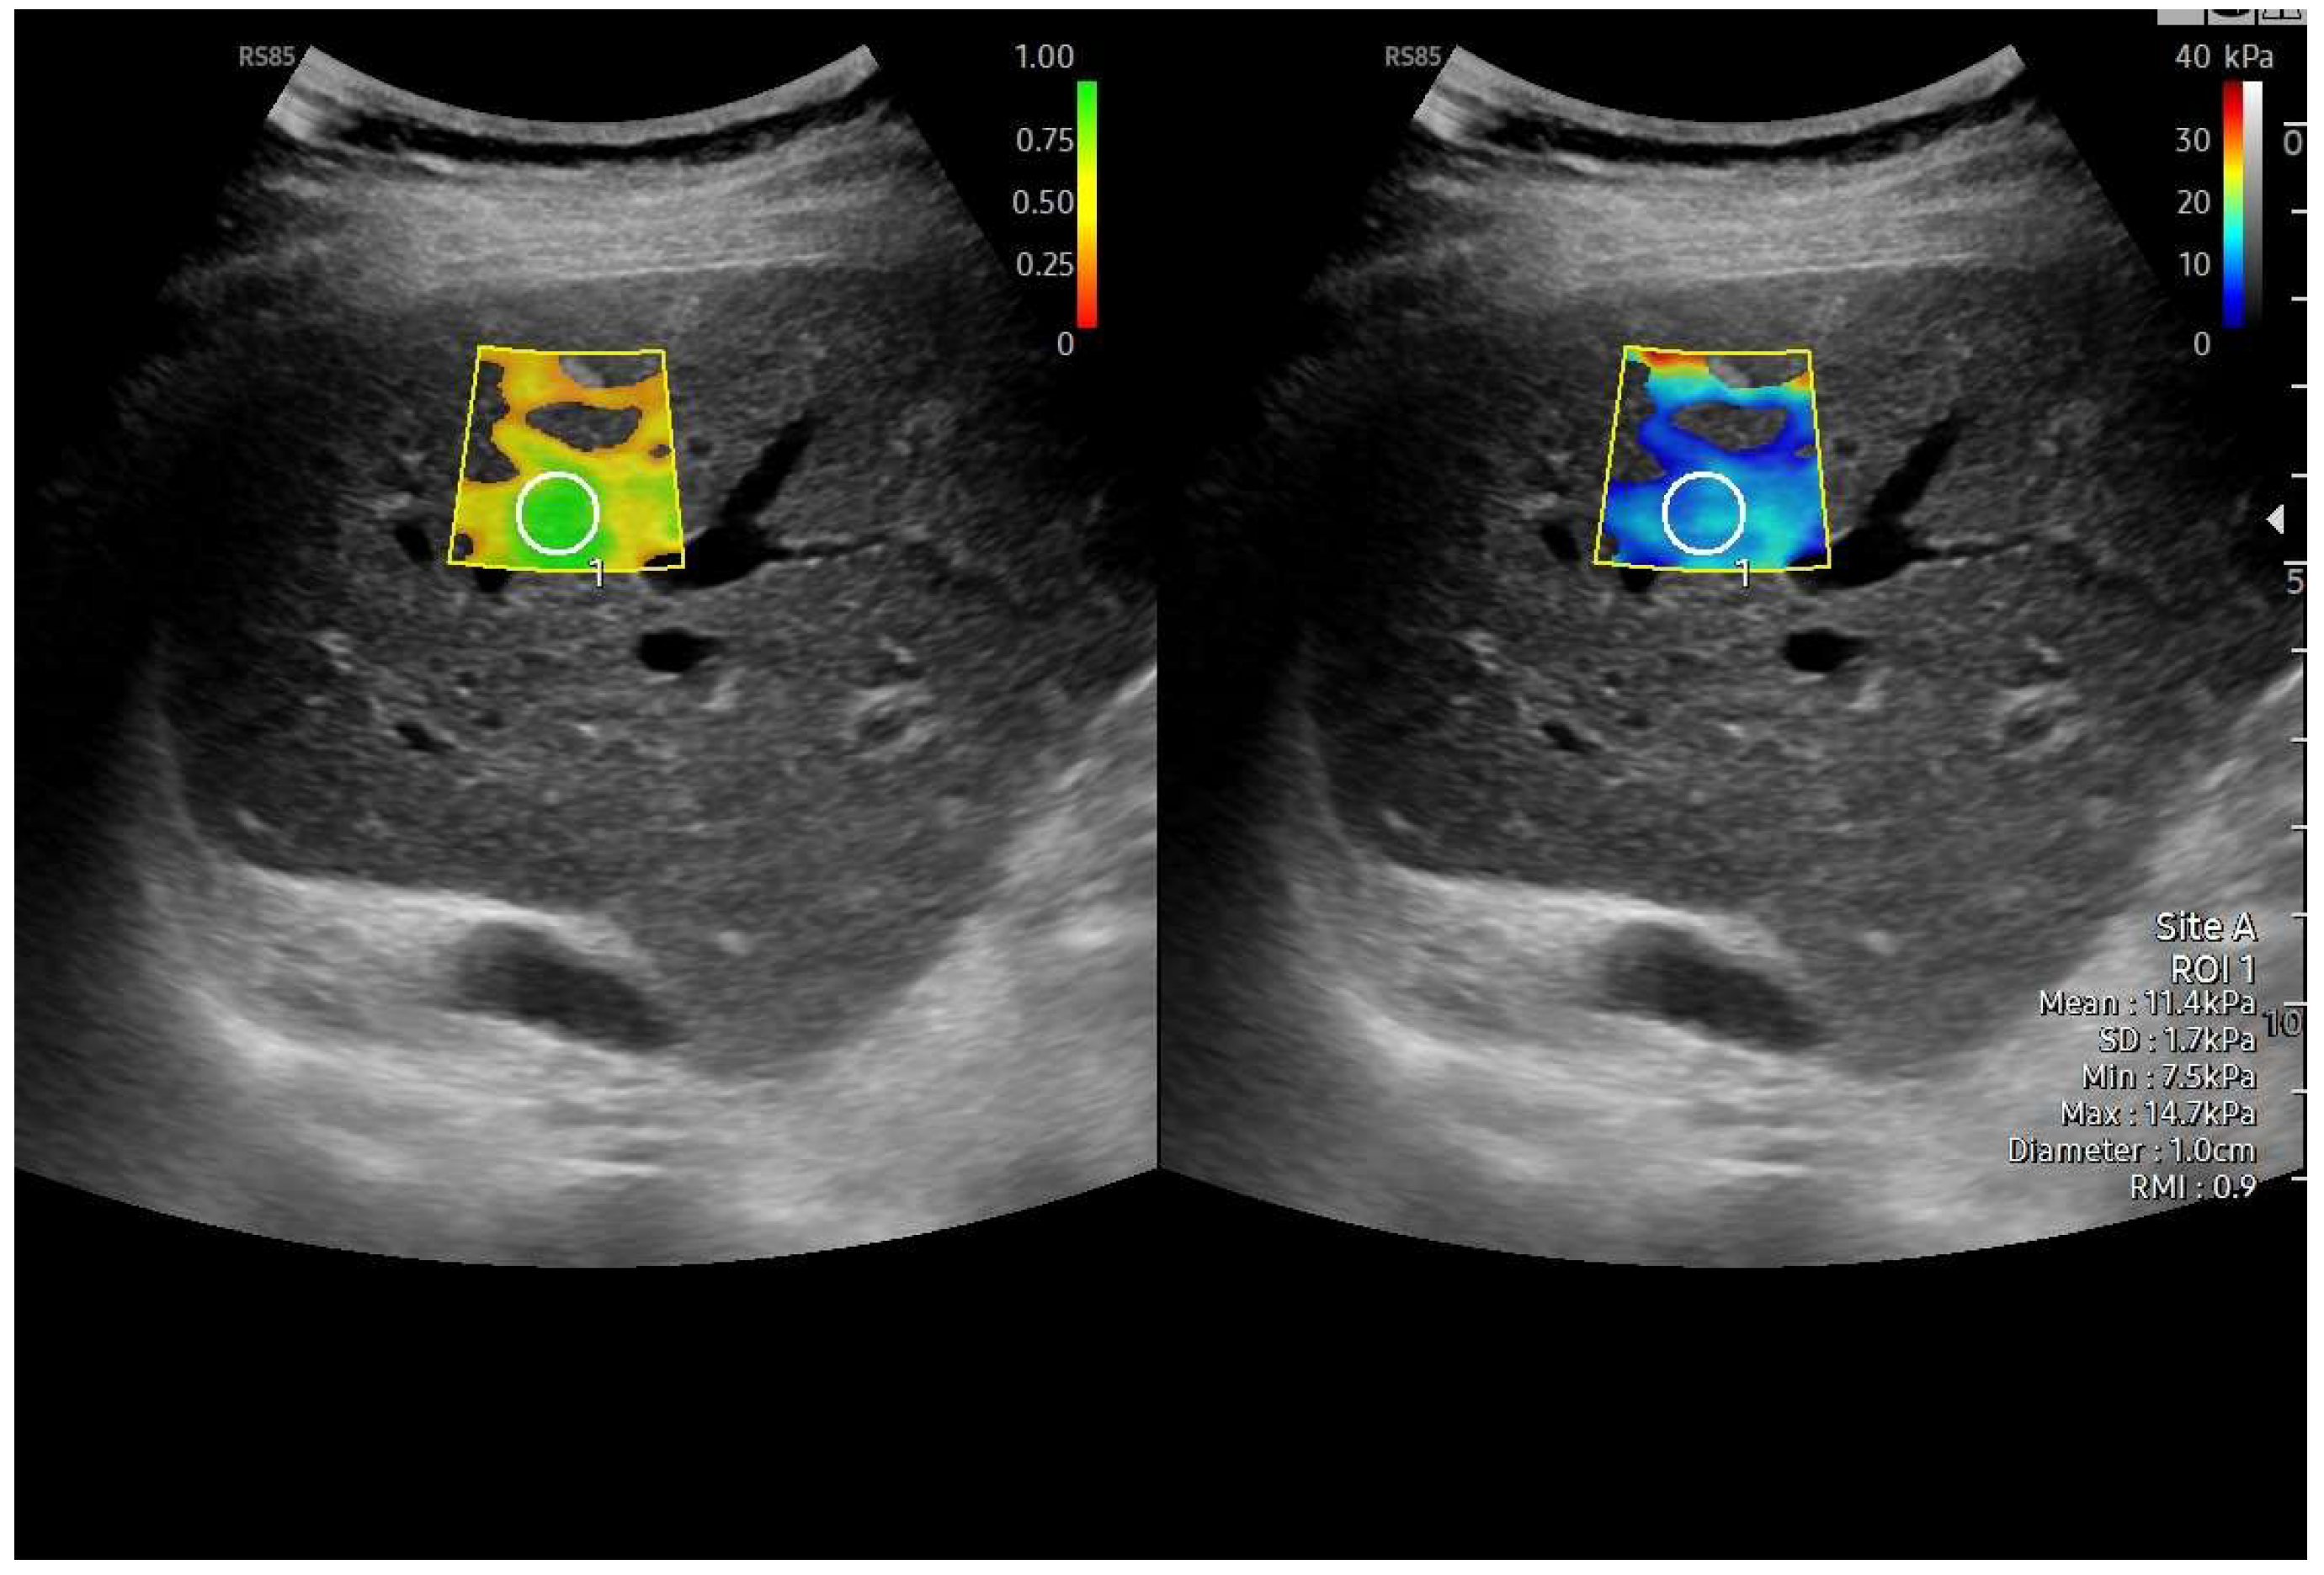

Different elastography techniques have been investigated for liver stiffness measurement (LSM) in Fontan patients, including point shear-wave elastography (also known as point radiation force impulse), two-dimensional shear-wave elastography imaging, transient elastography (TE) (Fibroscan®), and MR elastography (MRE) [90,91,92,93,94,95,96,97]. However, their application in Fontan patients remains challenging because systemic venous congestion can lead to an overestimation of LSM (Table 7). Fontan surgery results in an immediate increase in liver stiffness (LS) due solely to hepatic congestion [98] (Figure 20). Over time, signs of Fontan failure typically emerge, leading to further increases in LS values, which may exceed 15 kPa levels indicative of advanced disease stages in non-congestive liver diseases. In these cases, fibrosis progression may play a role [31,87]. Real-time tissue elastography (RTE) has been shown to reflect liver fibrosis in FALD from the early stages. When combined with hepatic vein waveform analysis, RTE has proven to be a valuable non-invasive tool for evaluating clinical conditions in FALD patients [37].

Figure 20.

Liver elastography performed using the 2D-SWE method. Left image: reliability color map of the elastography acquisition. The scale ranges from red (low reliability) to green (highest reliability), indicating that the shear-wave propagation in the sampled area was stable and technically adequate. Right image: quantitative stiffness measurement obtained from the region of interest (ROI), showing a mean value of 11.4 kPa with an IQR/M of 9%, consistent with F4 fibrosis in the clinical context of Fontan-associated liver disease.

US elastography, particularly shear-wave techniques, is increasingly being used for serial follow-up in these patients [11,99,100,101,102,103,104,105,106,107,108,109]. Longitudinal LSM assessment during follow-up could help monitor disease progression and predict clinical outcomes. However, elastography results must be interpreted with caution in the Fontan population, as no validated cut-off values for severe liver fibrosis exist for this specific group, unlike in other forms of chronic liver disease [11,99,100,101,102,103,104,105,106,107,108,109,110].